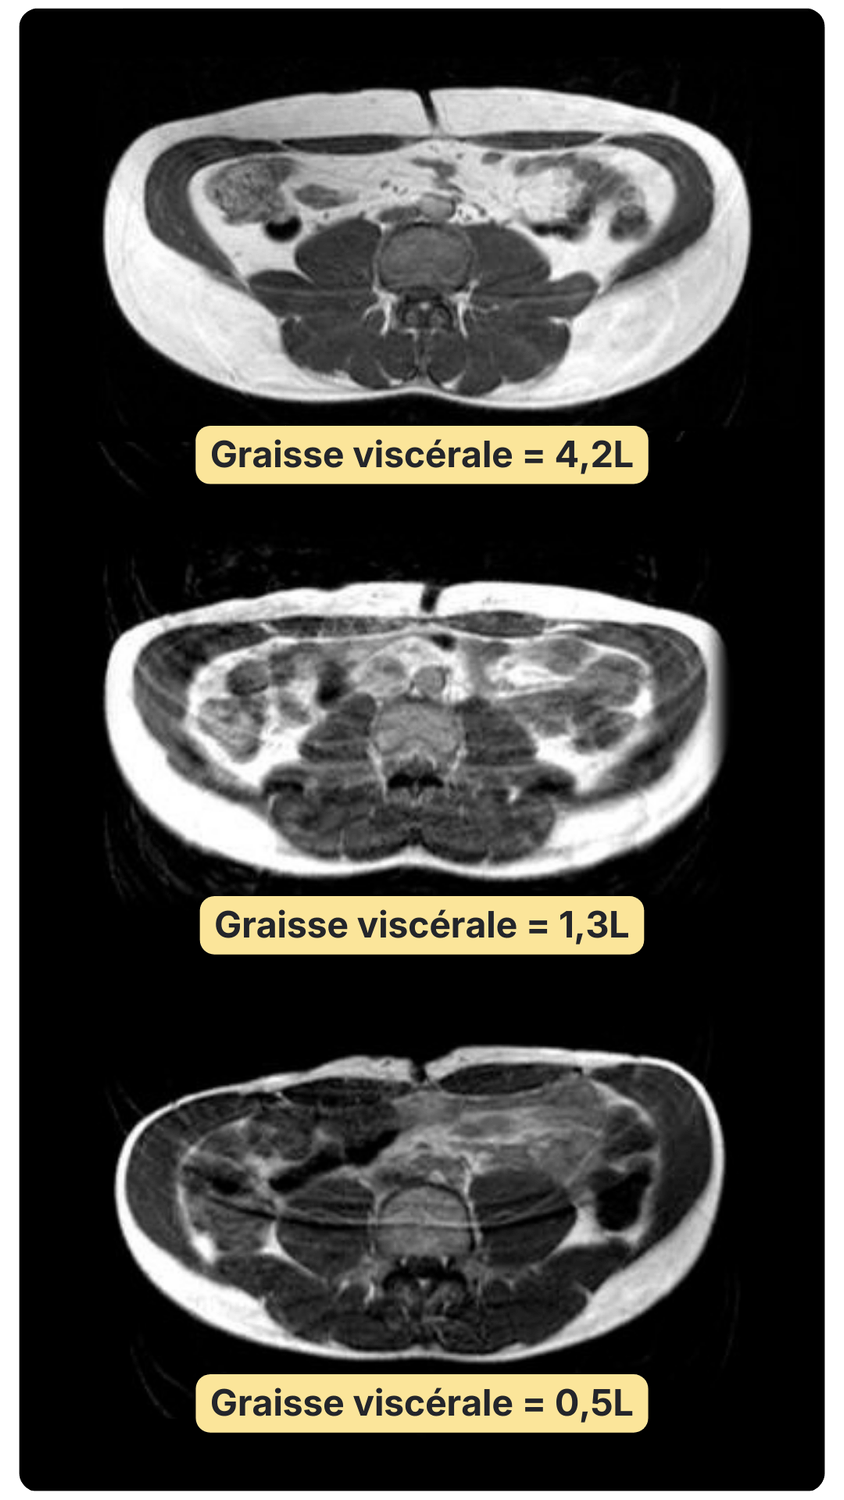

Réduction du foie gras